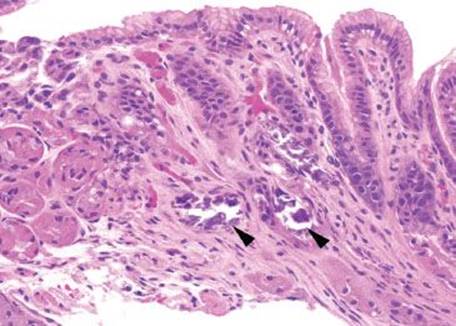

Gastric iron deposition is seen in up to 3.8% of upper tract biopsies (Fig. 2.228).23,24,183–185 In a study of 500 gastric biopsies, the deposition was demonstrated in three generalized patterns. Pattern A (also referred to as “nonspecific gastric siderosis”) was the most common subpattern and involved 2.2% of specimens (Figs. 2.229 and 2.230). This subpattern was associated with prior mucosal microhemorrhages, and the subtle depositions were predominantly identified within macrophages and stromal cells of the lamina propria. Pattern B (also referred to as “iron pill gastritis”) was seen in 0.8% of the biopsies and was consistently associated with ferrous sulfate therapy. This deposition was coarse and crystalline and predominantly identified in the extracellular and most superficial aspect of the biopsy (Figs. 2.231–2.234). In this subpattern, the background mucosa had a reactive gastritis/gastropathy pattern with erosions, ulcerations, and fibrino-inflammatory exudate common. In a separate study of 1,300 gastric biopsies, a similar “iron pill gastritis” injury pattern was detailed.184 This latter group reproduced the identical iron deposits in the laboratory by oxidizing ferrous sulfate tablets, providing clear evidence for the iron origin of these deposits. The mechanism of injury is a bit unclear in this subpattern. Some speculate that the iron pill has a direct caustic effect on the adjacent mucosa, whereas others suggest that the iron deposits may simply colonize previously injured mucosa. Pattern C (also referred to as “gastric glandular siderosis”) was the least common pattern, involving 0.6% of the specimens. This subpattern was associated with iron overload settings, such as hereditary hemochromatosis and multiple blood transfusions. The characteristic deposits were subtle, uniform, and identified in the deep antral and oxyntic glands (Figs. 2.235–2.239). The iron deposits can be highlighted blue with a Prussian blue iron special stain. Recognition is important to help prevent further injury and potential stricture formation (pattern B), to suggest pertinent iron overload evaluation (pattern C), and to avoid overdiagnosing the marked reactive epithelial change as dysplasia.

Figure 2.229 Iron pattern A/“nonspecific gastric siderosis”. This is the most common iron pattern of injury, and it can be easy to miss on low power. Scattered pigment laden macrophages and stromal cells are seen (arrowheads), characteristic of the iron pattern A/nonspecific gastric siderosis pattern. Prior mucosal damage and microhemorrhages account for these findings.